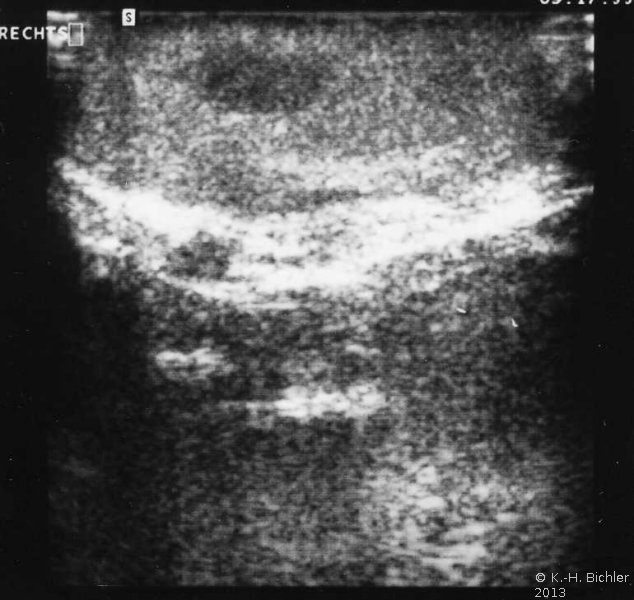

In der Sonographie finden sich abgekapselte Tumoren (Abbildung 6).

Noduläre Leydig-Zell-Hyperplasien sind in der Sonographie ebenfalls als umschriebene Tumoren erkennbar (Abbildung 7).

Anamnestisch bestand bei dem Jugendlichen bereits seit über einem Jahr eine beiderseitige Gynäkomastie. Die körperliche Untersuchung ergab einen derben Tumor am Oberpol des rechten Hodens. Beide Hoden insgesamt klein. Die Sonographie zeigte im rechten Hoden ein inhomogenes, umschriebenes tumorverdächtiges Areal (Abbildung 7a). Im Spermiogramm fand sich eine Oligozoospermie (< 1.000.000/ml). Die Tumormarker AFP und β-hCG im Normbereich. Die Werte von Testosteron, FSH, LH und Östradiol siehe Kurve. Auffällig war die Östradiolerhöhung (Abbildung 8).

Bei dem jungen Erwachsenen bestand ein männlicher Pseudohermaphroditismus (Reifenstein-Syndrom) mit deutlich verkleinerten Hoden, Hypospadie und Gynäkomastie. Sonographisch fiel im rechten Hoden ein hypodenses tumorverdächtiges Areal auf (Abbildung 1). Die daraufhin erfolgte Hodenfreilegung und Biopsie ergaben zunächst die Diagnose Leydig-Zell-Tumor, nach weiteren Untersuchungen noduläre Leydig-Zell-Hyperplasie (Abbildung 9).